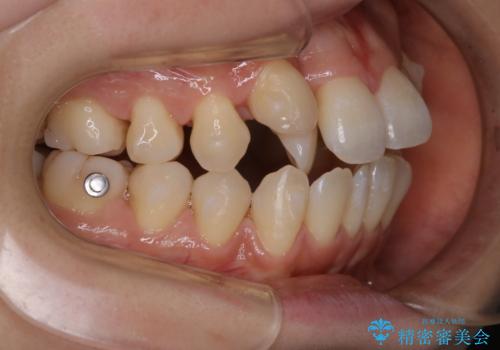

- インビザラインで矯正中に着色や歯石がついてしまったためクリーニングをしたいとのことで来院されました。

PMTC60分コースを行いました。

コーヒーによる頑固な着色や磨き残しによる歯石が多く付着していました。マウスピースをつけたままコーヒーを飲むこともあるそう。その場合は、なるべくはやくに歯磨きをしてマウスピースもしっかりと洗いましょう。